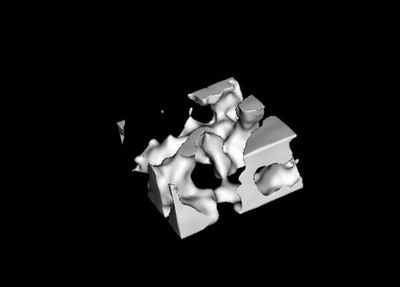

Micro–Computed Tomography is based on Cone Beam Computed Tomography which is a imaging modality used in hospital CT scans or angiography units, but on a small scale with increased resolution. Theses systems are used for non destructive 3D microscopy. We build our own system where we employed our own x-ray detectors. The system has resolution of 8 microns and uses a control software and reconstruction developed by our staff. The system has been used for endovascular devices integrity study, bone structure, tumor imaging, etc.

The bone is a complex tissue which regulates its mass and architecture to satisfy the structural and metabolic necessities. The bone structure the body framework and it serves as a mineral reservoir. Our Micro-CT system has been extensively used to scan bone structures. Our home built detectors provide extremely high resolution and sensitivity unmatched by current flat panel technologies. We provided vital data to research groups working in dentistry, regenerative materials, implants and ageing. In addition to raw data we developed software which can calculate various morphological parameters such as: bone surface, trabecular volume, trabecular thickness, trabecular separation number and fractal dimension.